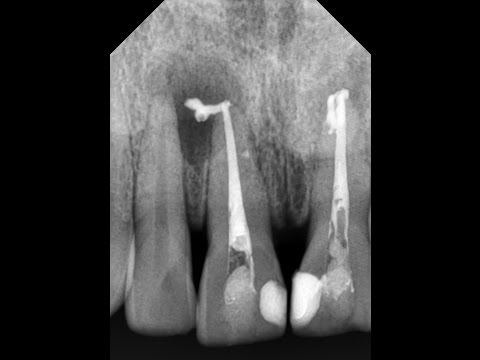

как часто вы приходили к врачу за протезированием зубов, а он говорил, что необходимо зубы перелечить? Вы думаете это развод? В этом видео я хочу вам рассказать для чего необходимо перелечивать зубы перед постановкой коронок и протезирования зубов